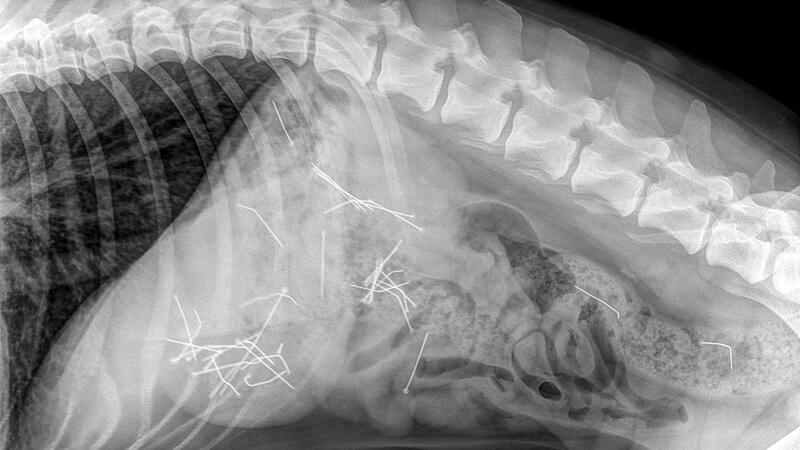

Das Röntgenbild zeigt deutlich die vielen Stecknadeln im Körper der Hündin.

Tierarztpraxis Beck.

Coburg – Beim Gassigehen hat die Hündin den Köder gefressen. Ein Psychologe erklärt, was in Menschen vorgeht, die solche Fallen auslegen.